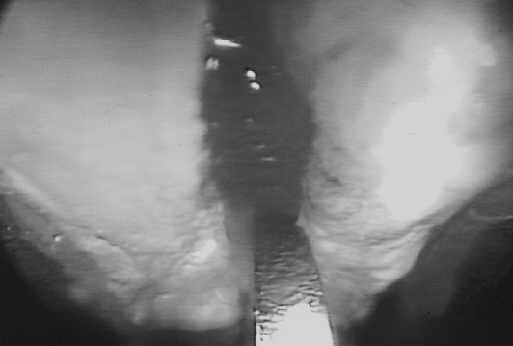

Wir führen die endoskopische Spaltung des Karpalbandes in 2-Portal-Technik modifiziert nach Chow durch. Die Operation erfolgt ambulant in Lokalanästhesie ohne Anlage einer Blutleere. Der Eintrittsport befindet sich in der proximalen Handgelenksfalte (Restricta) ulnar der Palmaris-longus-Sehne. Der Austrittsport liegt ca. 4-5 cm distal der distalen Handgelenksfalte (Rascetta) in Richtung auf die Basis des Ringfingers (Abb. 1). Während der Operation wird die Hand im Handgelenk extendiert, um die Sehnen und den Medianus vom Band fernzuhalten. Zunächst wird am Eintrittsport die Unterarmfaszie dargestellt und inzidiert. Anschließend wird mit einem Dissektor in den Karpaltunnel eingegangen. Man tastet deutlich die typische Waschbrettstruktur der derben queren Bandfasern. Zunächst erfolgen die Inspektion des Bandes mit der 30°-Grad-Optik und die Identifizierung des distalen Bandendes. Synoviales Gewebe auf dem Band wird mit einer Knopfsonde abgeschoben, bis man freie Sicht auf das Band hat (Abb. 2). Die Durchtrennung des Bandes erfolgt von distal nach proximal mit dem Hakenmesser (Abb. 3). Aufgrund der Banddicke sind in der Regel mehrere Schnitte bis zur vollständigen Durchtrennung erforderlich.

Abb. 2: Endoskopischer Blick auf das Retinaculum flexorum